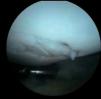

Figura 7 Artroscopia. Cuerpos libres alrededor del ligamento cruzado íntegro.

Figura 8 Artroscopia. Cuerpos libres alrededor del ligamento cruzado íntegro.

Se practica artroscopia, en la que se observan (figs. 2, 4, 6-8):

• Múltiples fragmentos condrales libres de bordes agudos, que se identifican como recientes y de bordes redondeados que se catalogan como antiguos.